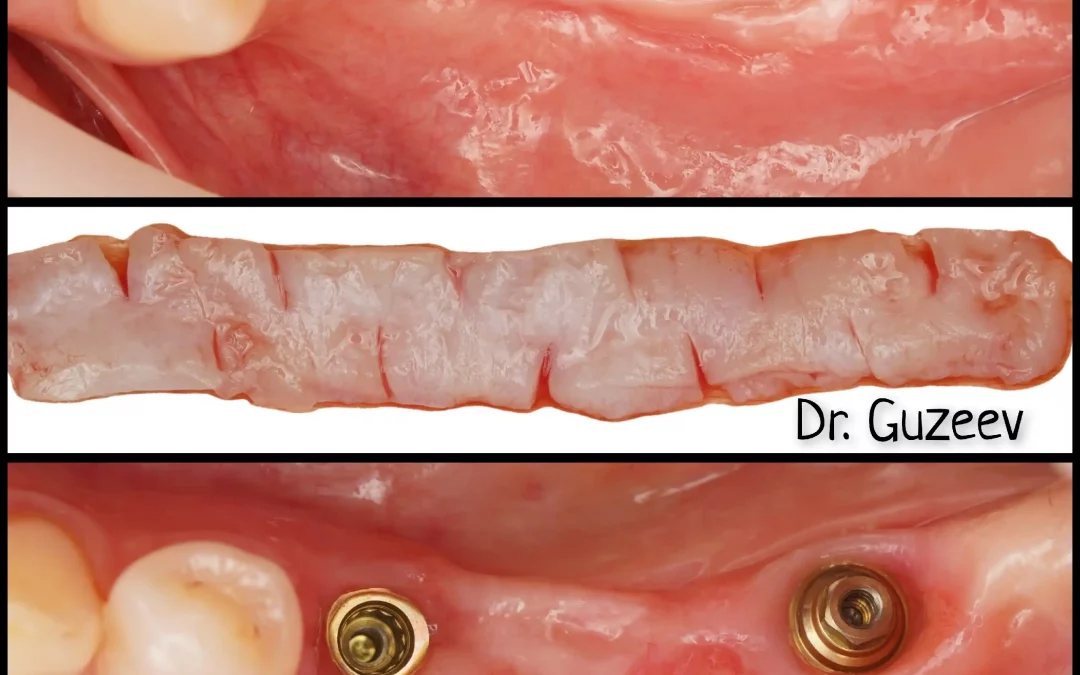

Юрий Гузеев | Клинический кейс YG-130

Подвижность зубов, периодонтальные изменения - Удаление, имплантация MIS C1 . - Два трансплантата. - Коронально смещенный лоскут для коррекция зенитов. - Connect абатмент + временные...